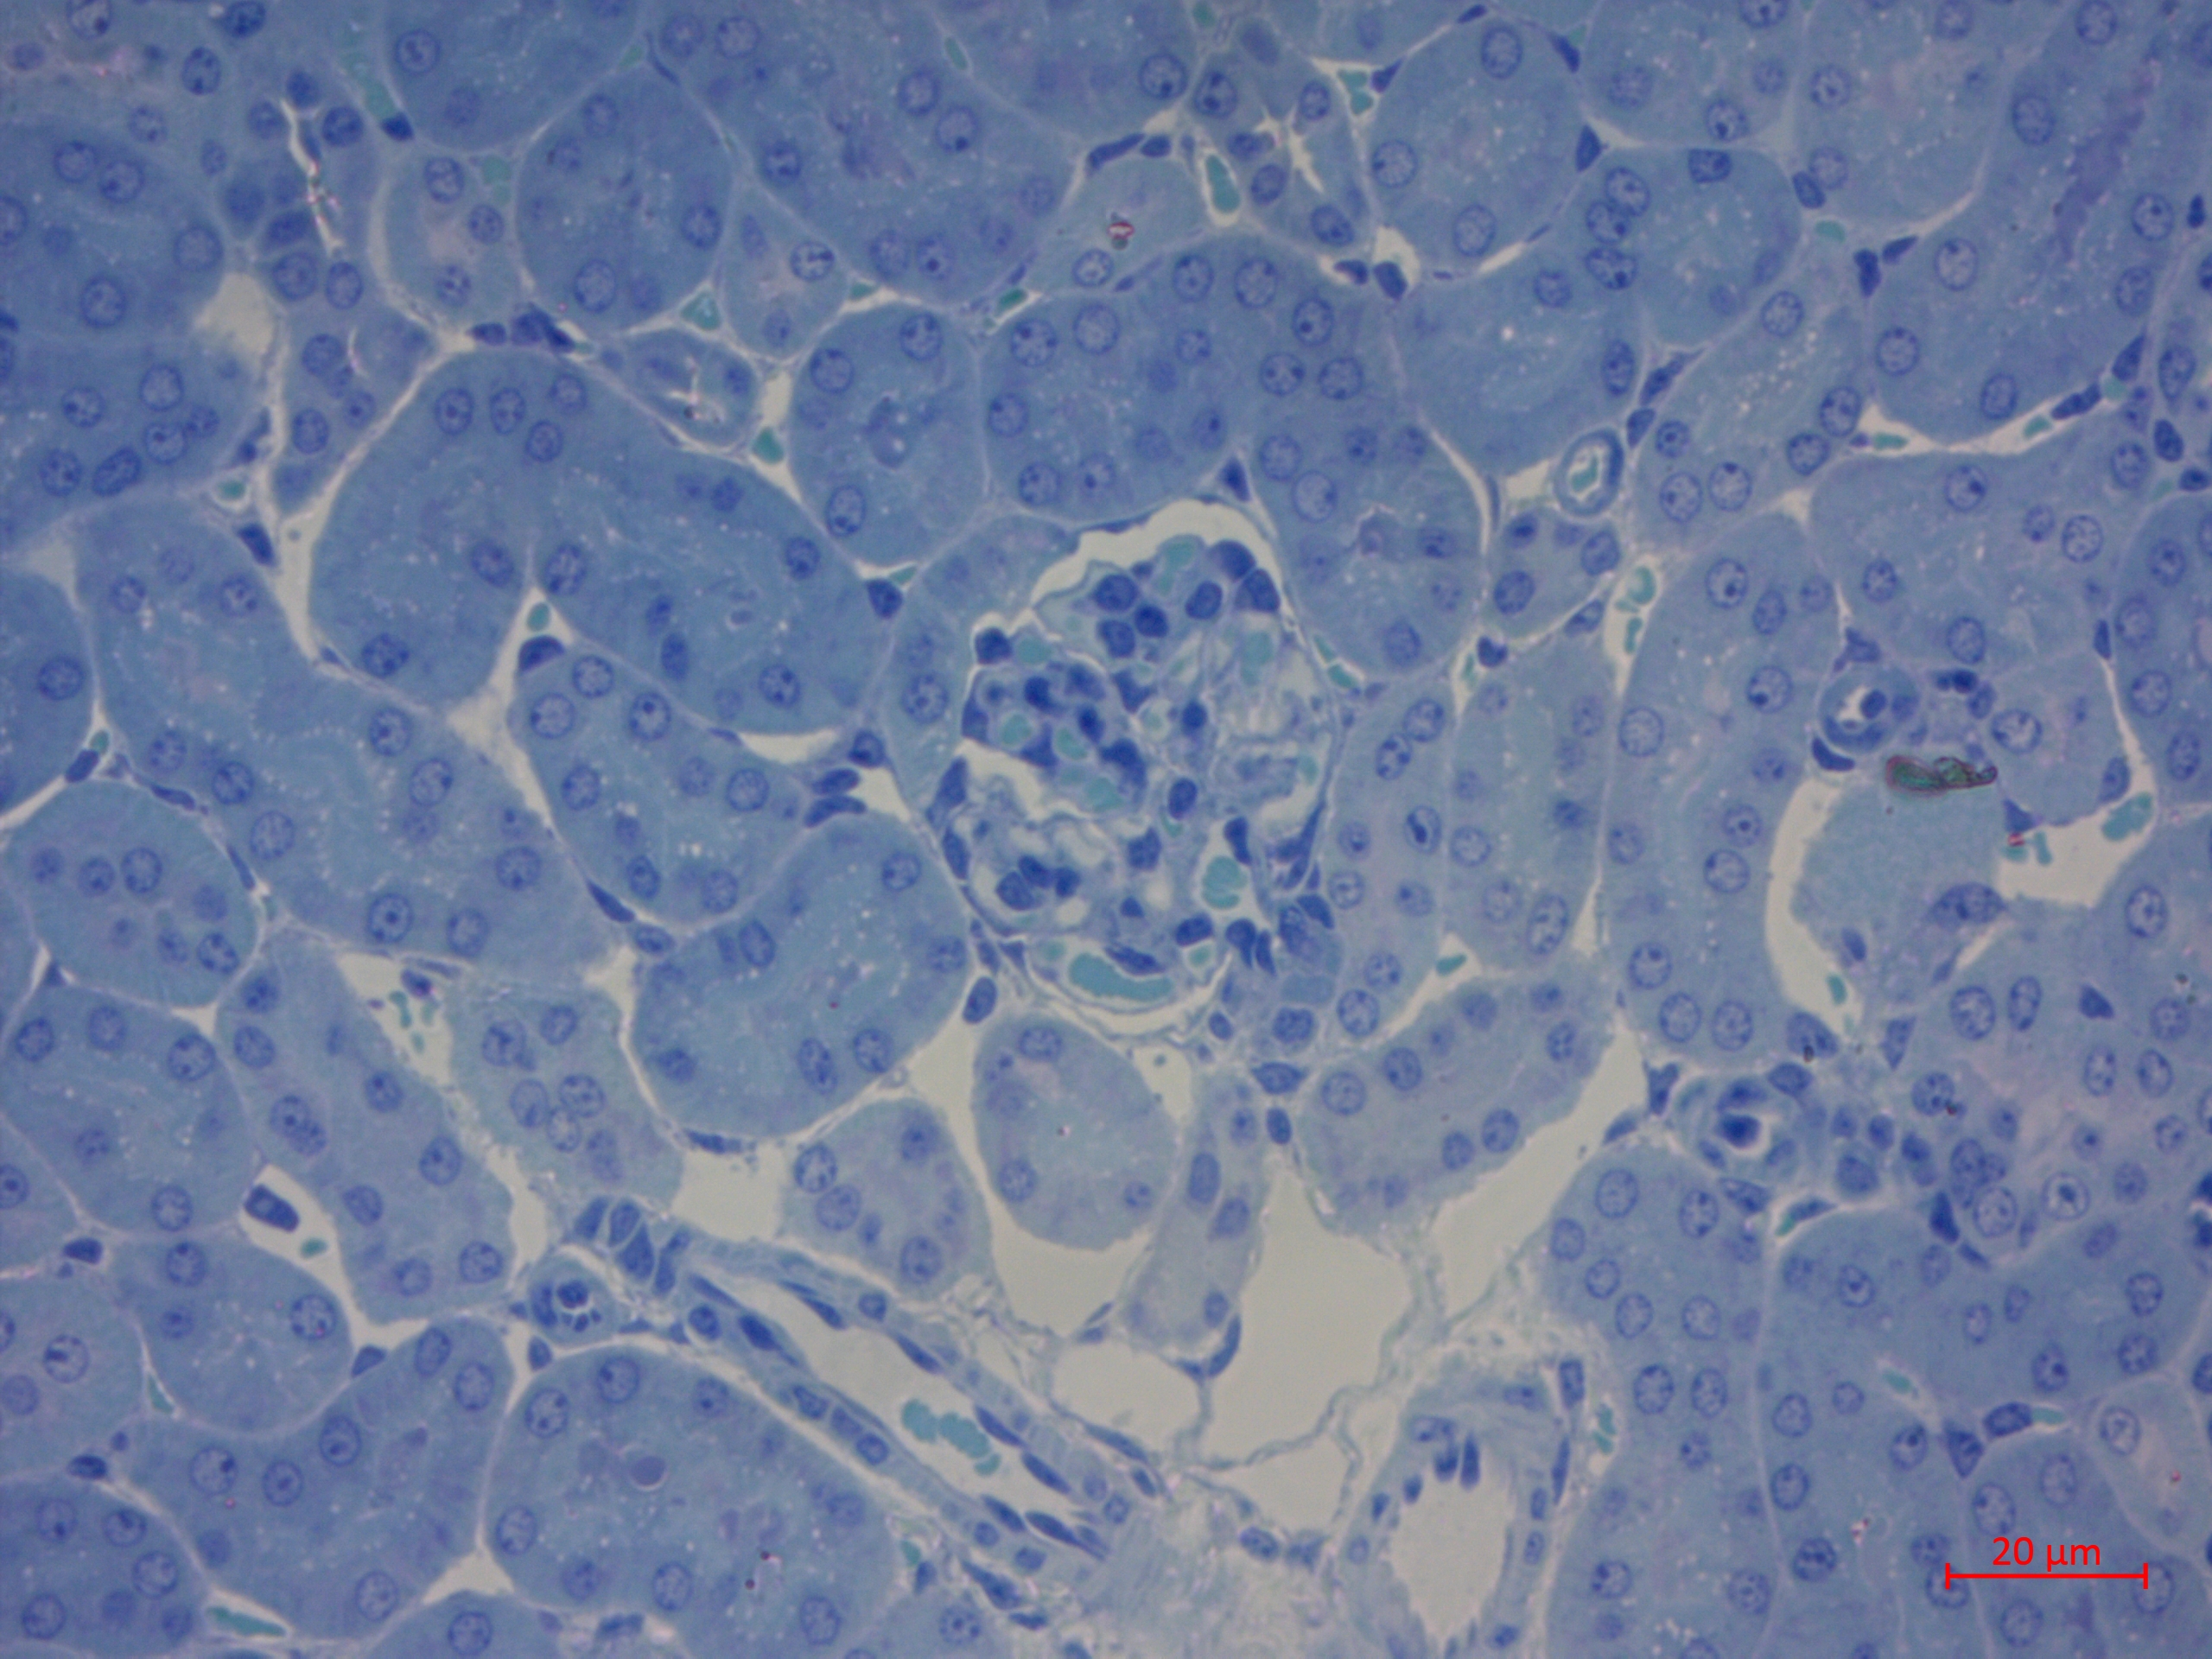

4. Рис. 2. Почка морской свинки при острой декомпрессионной болезни. Мелкодисперсная вакуолизация и более крупная вакуолизация в структурах нефронов. Стаз капилляров микроциркуляторного русла почечного тельца. Полутонкий срез. Окраска толуидиновым синим. Масштабный отрезок – 20 мкм. | |